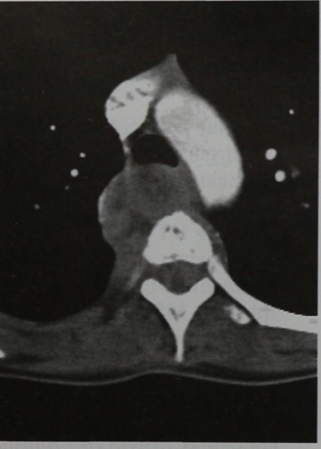

(Слева) Сагиттальный срез, Т1-ВИ: саркома Юинга, практически полностью поражающая тело L5 позвонка и распространяющаяся в эпидуральное пространство. Линия низкой интенсивности сигнала представляет собой не границу опухоли, а зону реактивного склероза. Опухоль в Т1 -режиме характеризуется относительно низкой интенсивностью сигнала по сравнению с красным костным мозгом и мышцами.

(Справа) Аксиальный КТ-срез, этот же пациент: более четко визуализируется зона реактивного остеосклероза в толще опухоли. Видны признаки распространения опухоли в паравертебральные ткани.